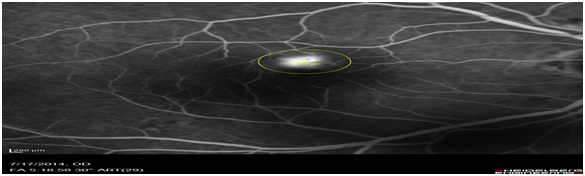

Images of patients (n=63) of patients who had classic type 2 CNV was retrospectively analysed. OCT images obtained on the Heidelberg spectral is at diagnosis were compared to the FFA images obtained on the same day. The OCT biomarker, the sub retinal hyper reflective mass (SRHRM) was used. The same photographer was used to minimise bias. The sub retinal hyper reflective mass was used as the OCT biomarker. The size of this SRHRM was measured at its widest using the caliper setting. This was then compared to the widest diameter of the CNV leakage measured on ultra high-resolution spectral is FFA by drawing a circle around the leage and noting its diameter (Figure 1A,1B & 2A,2B).

Figure 1B Measurement of the CNV lesion in the early phase of the FFA scan (1504m).